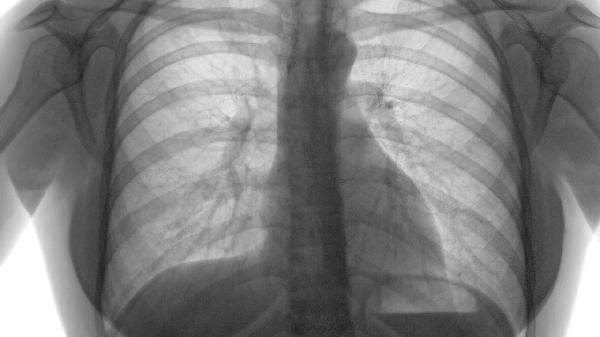

如何治療肺氣腫

肺氣腫可通過戒煙、氧療、藥物治療、肺康復(fù)訓(xùn)練、手術(shù)治療等方式治療。肺氣腫通常由長期吸煙、空氣污染、遺傳因素、職業(yè)粉塵接觸、反復(fù)呼吸道感染等原因引起。